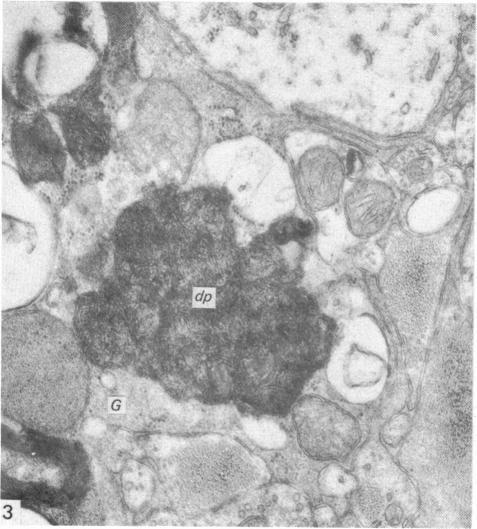

The ultrastructural changes following a single intracisternal injection of 6-OHDA were studied in the intermediolateral nucleus of the monkey spinal cord. Post-operative survival periods ranged from 20 hours to 14 days. At all stages, only boutons containing clear, round vesicles (R-boutons) and those containing dense-cored vesicles (DCV-boutons) underwent degeneration. Boutons containing flattened vesicles (F-boutons) appeared to be unaffected. Changes were seen even at 20 hours after injection and these were confined to R-boutons only. The changes included an initial swelling and crowding of the vesicles, followed by an increase in the electron density of the axoplasm. The latter change was most marked on the second post-operative day and by the third day, most of the electron-dense profiles were glia-engulfed. By the third day, also, many unmyelinated and, occasionally, myelinated axons showed accumulations of mitochondria, membrane-bound tubular profiles and electron-dense bodies. Many astrocytic processes also showed accumulation of tubular profiles. From the fifth day onwards, few degenerating R-boutons were encountered but DCV-boutons containing swollen vesicles, with or without their dense cores, were obvious. Unmyelinated and, occasionally, myelinated axons and astrocytic processes containing tubular elements still continued to be seen. By the fourteenth post-operative day, degenerating profiles were rarely observed. The probable significance of these findings has been discussed in the light of recent anatomical and biochemical studies.

在猴脊髓中间外侧核中,研究了单次脑池内注射6-羟基多巴胺(6-OHDA)后的超微结构变化。术后存活期从20小时至14天不等。在所有阶段,只有含有清亮圆形囊泡的终扣(R终扣)和含有致密核心囊泡的终扣(DCV终扣)发生退变。含有扁平囊泡的终扣(F终扣)似乎未受影响。甚至在注射后20小时就可见到变化,且这些变化仅局限于R终扣。变化包括囊泡最初肿胀和聚集,随后轴浆电子密度增加。后者的变化在术后第二天最为明显,到第三天,大多数电子致密图像被胶质细胞吞噬。同样在第三天,许多无髓鞘以及偶尔有髓鞘的轴突显示出线粒体、膜结合管状结构和电子致密体的聚集。许多星形胶质细胞突起也显示出管状结构的聚集。从第五天起,很少遇到退变的R终扣,但含有肿胀囊泡(有或无致密核心)的DCV终扣很明显。仍可继续见到含有管状成分的无髓鞘以及偶尔有髓鞘的轴突和星形胶质细胞突起。到术后第十四天,很少观察到退变图像。已根据最近的解剖学和生物化学研究对这些发现的可能意义进行了讨论。